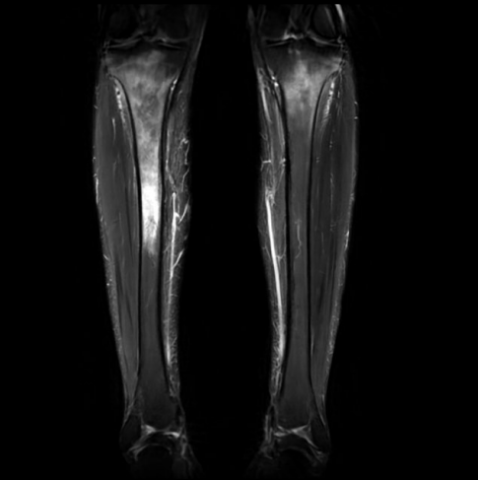

Séquence sagittale.png

Séquence sagittale DP FS montrant un oedème

médullaire osseux s’étendant de l’épiphyse à la

métaphyse et à la diaphyse.